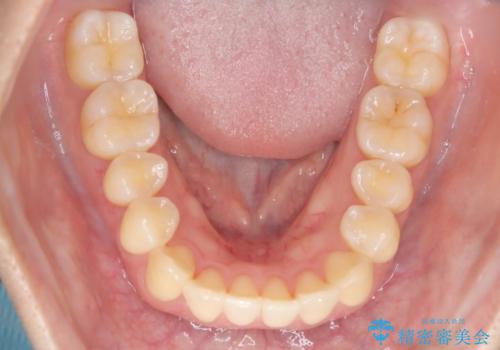

【インビザライン】反対咬合を治したい

- 前歯の反対咬合を主訴に来院されました。

インビザラインにて歯列弓の拡大により叢生の改善を行うことができ、患者様にも満足していただました。

前歯の反対咬合は歯牙への負担も大きくできるだけ早期に治療を行うことを推奨しています。